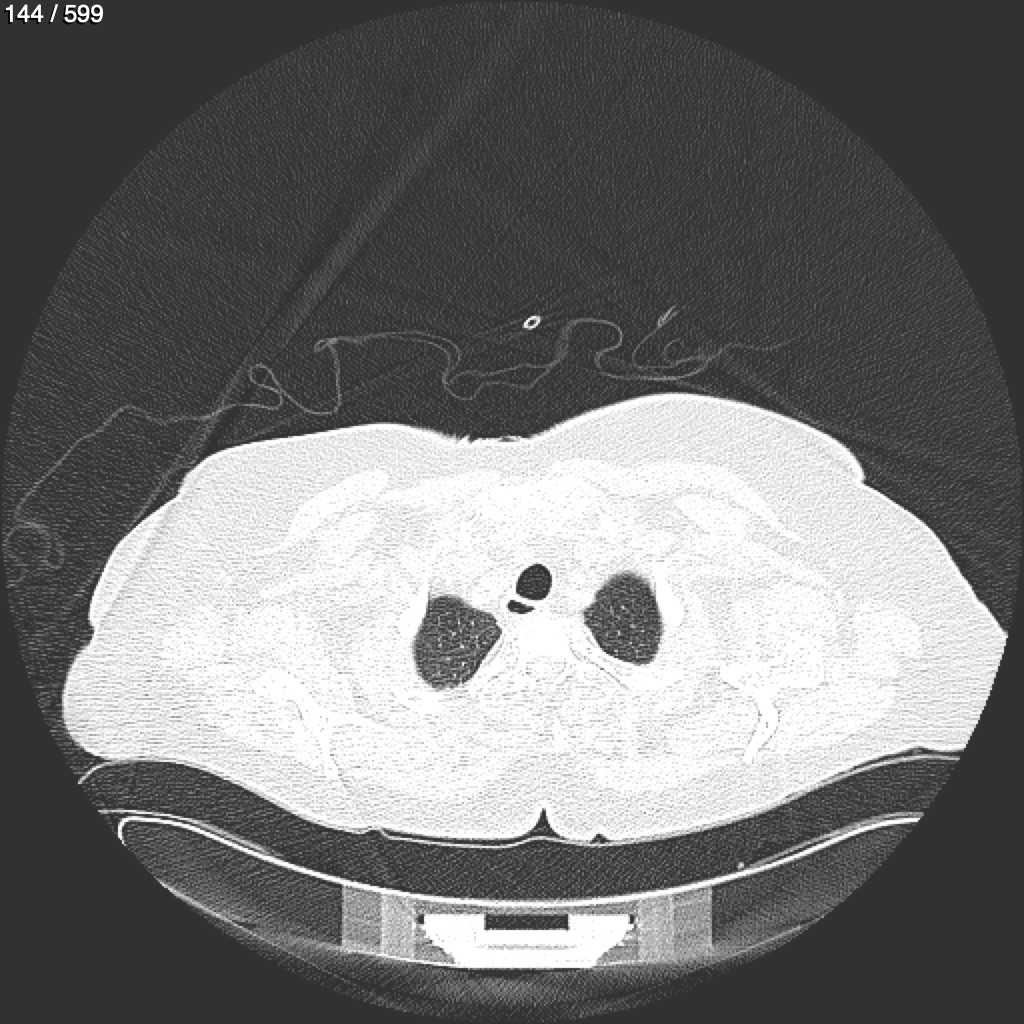

Home G​l​o​r​i​a​ ​G​l​a​d​y​s​ ​B​e​a​s​l​e​y​ ​-​ ​T​ó​r​a​x​ ​T​o​r​a​x​_​S​i​m​p​l​e​ ​(​A​d​u​l​t​o​)